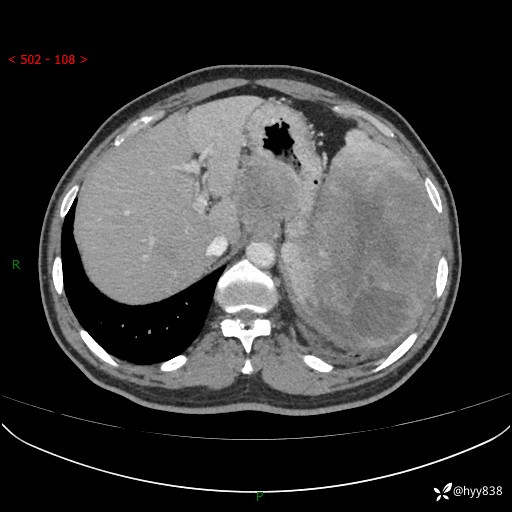

上腹部CT平扫